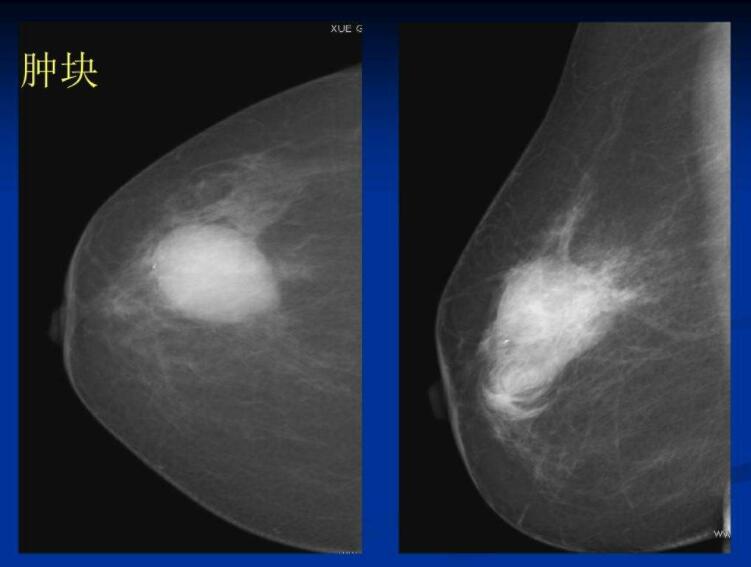

《自然》学术期刊进行的研究表明,人工智能根据乳腺X线影像对乳腺癌做出的诊断比医生更准确。

由谷歌健康部门和伦敦帝国理工学院科研人员组成的一个国际科研小组在分析了2.9万名妇女的乳腺X线影像后研制出一个电脑模型。

试验时使用了匿名人士的照片。目前,医院里的一名女性患者乳腺X线影像通常由两名专家共同分析。极少情况下会有第三名医生介入。与此同时,医生为了能正确解读乳腺X线影像,需要接受10年以上的专业培训。

新的专业电脑模型在正确诊断率上与两名一起工作并熟悉患者病史的医生相同。